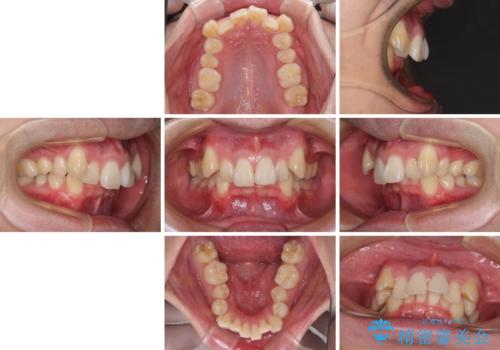

- 八重歯を気にして来院された患者様です。

顕著な上顎の八重歯とディープバイトであったため、上顎の左右第一小臼歯を抜歯することとしました。

犬歯歯根の位置や奥歯の咬み合わせから、ワイヤー装置での治療を強くおすすめいたしましたが、ご本人の強い希望により、妥協的な仕上がりとなることを了解いただき、インビザラインにて矯正治療を行うこととしました。

インビザライン単体で、左右ともに移動の難しい位置に歯根のある犬歯を整えるのは困難と判断し、補助装置を併用することとしました。

ディープバイトや奥歯の咬み合わせなど、インビザライン矯正では限界がありワイヤー装置での治療に及ばない仕上がりとなりました。

ただし、患者様としては八重歯や、それに伴う唇の閉じにくさが改善されたとのことで、納得いく状態での治療終了となりました。